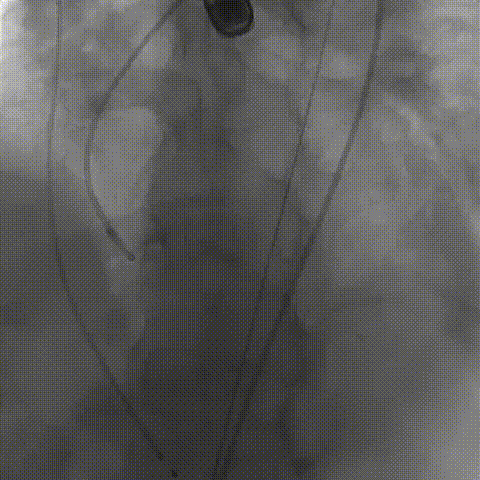

根部造影;直头导丝顺利跨瓣

23mm球囊预扩,冠脉显影正常;输送器顺利过弓